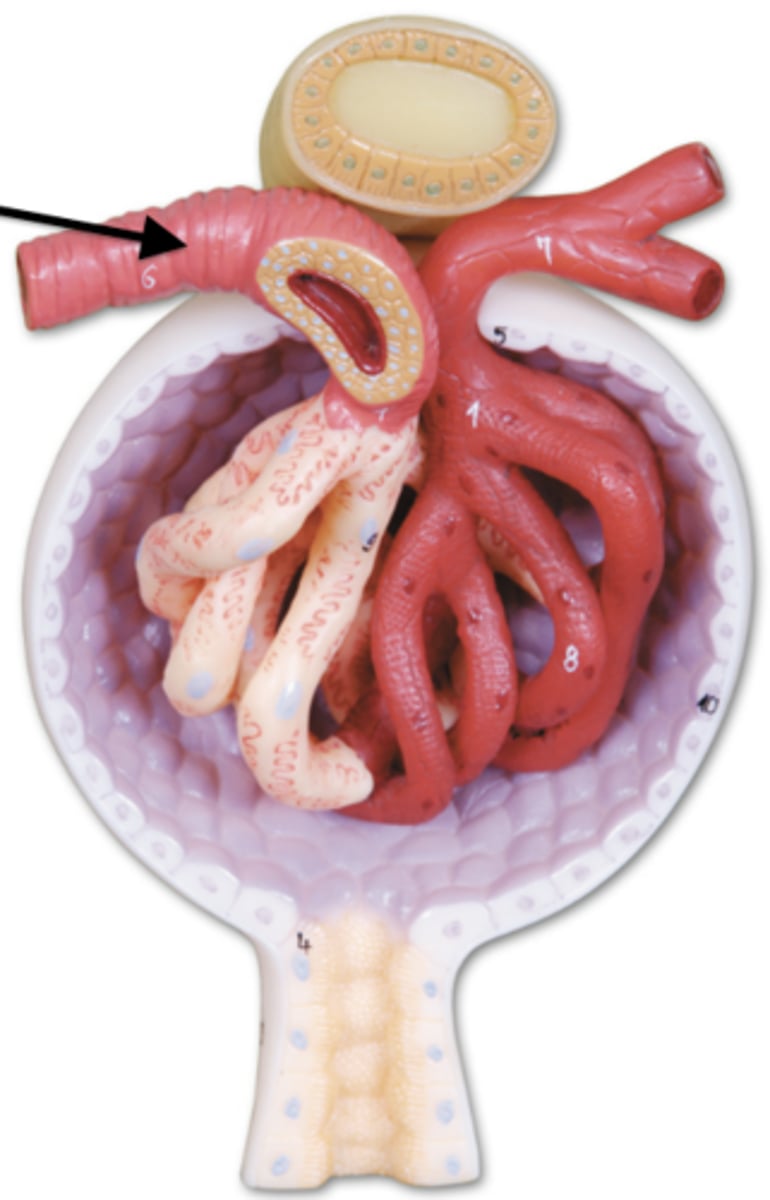

arrow

afferent arteriole

efferent arteriole

glomerulus

juxtaglomerular apparatus

Bowman's capsule / glomerular capsule

macula densa cells

cells

juxtaglomerular cells

cells

podocytes

cells

capsular space

the cavity

renal corpuscle

proximal convoluted tubule

descending loop of henle

ascending loop of henle

distal convoluted tubule

papillary duct

collecting duct